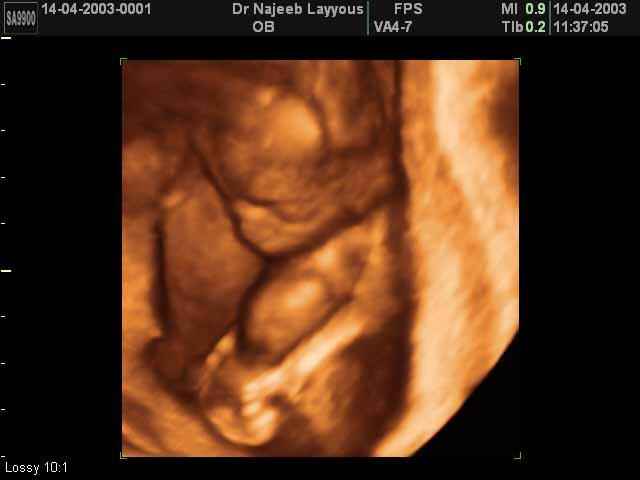

- Fetal Parts Ultrasound Scan Photos

3D Second Trimester Ultrasound Scan Photos-second part of pregnancy | Dr N Layyous